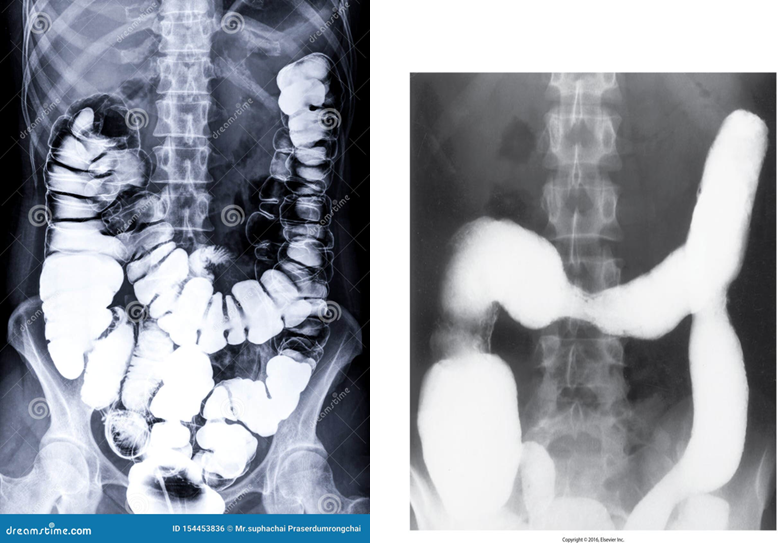

Ulcerative Colitis

is an idiopathic inflammatory disease of the bowel.

Begins in recto-sigmoid area

It causes long term inflammation of the colon and rectum.

Increased risk of malignancy is also associated.

Involves mucosal layer of colon.

Radiological Appearance:

Double contrast barium enema of early __ show fine granularity of the mucosa.

Double contrast barium enema of chronic __ show a Lead pipe sign (colon). The diseased segment of the colon exhibits a complete loss of pouch markings, resulting in a smooth-walled, cylindrical appearance.